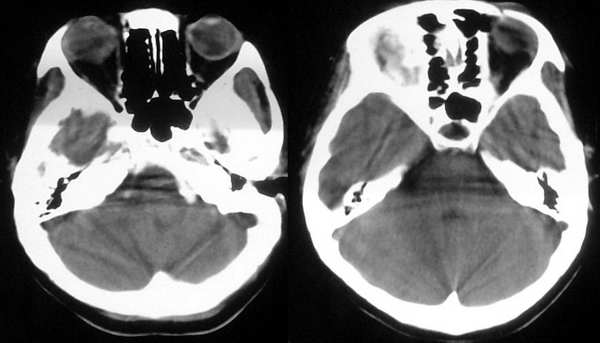

患者,女,32岁,时有头晕,无恶心呕吐。

这个病例为正常的头部ct表现,只是由于摆位不正而造成了诸多疑问,所以在工作中要注意摆位问题。

我认为是正常的颅脑影像。左侧颞顶叶脑组织示略高密度结构是近外侧裂区的正常皮质结构,不是灰质移位。由于摆的位置不正,左侧的脑组织较右侧的低一个层面。